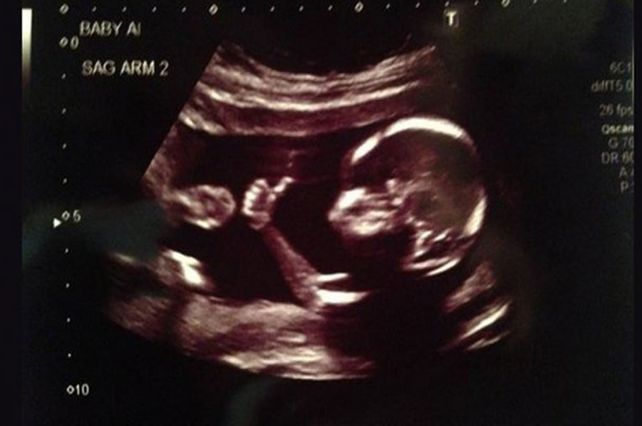

Una increíble imagen muestra a un bebé en la panza de su mamá, en plena ecografía, levantando el dedo pulgar, como en una señal de aprobación.

Su padre fue quien capturó la imagen mientras el médico revisaba cómo seguía el embarazo.

El padre de la criatura subrayó que el material es real y confirmó que la misma fue tomada el pasado 27 de agosto.